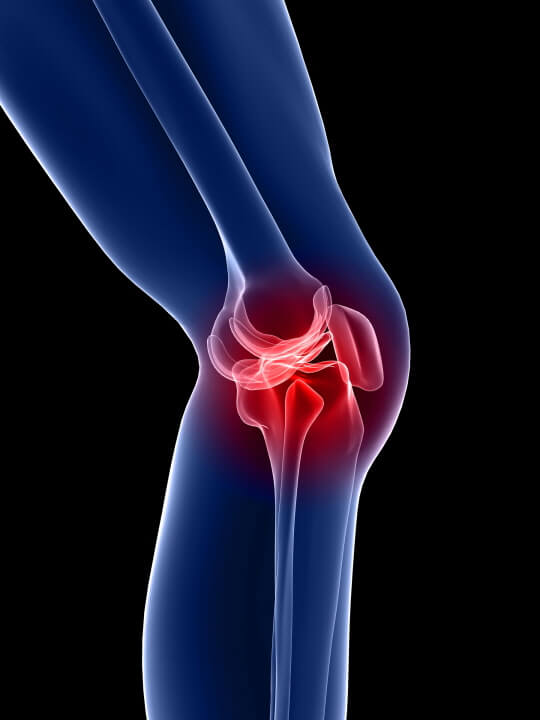

무릎 관절염 원인

무릎 관절염은 여러가지 원인에 의해 발생할 수 있습니다. 가장 일반적인 원인은 연령과 함께 발생하는 자연적인 연골 손상이며, 무릎 관절 과부하, 외상, 근육과 연조직의 약화, 대사성 질환, 유전적 요소 등이 원인이 될 수 있습니다.

1. 연령: 연령이 들어갈수록 무릎 관절의 연골이 더 얇아지고 마모되는 것은 자연스러운 일입니다. 이로 인해 노화성 관절염(오스테오아르트리티스)이 발생할 수 있습니다.